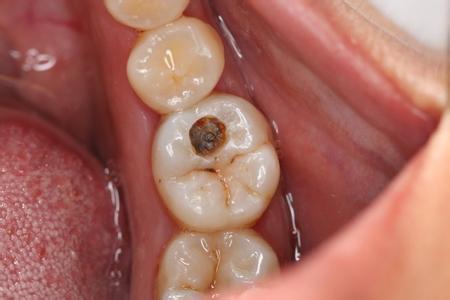

求美者:周茹医生,*近总是牙疼,照镜子发现有好几个黑洞,应该怎么办啊?

周茹:您这是龋齿现象,得及时治疗避免情况加重。

1.牙痛:館洞较大,损伤牙神经时会导致疼痛;

2.牙齿缺失:已形成较大牙洞的龋齿,无法修复.只能进行拔牙治疗: 3.影响咀嚼:牙齿館坏后,咀嚼功能降低,影响食物的消化和吸收。